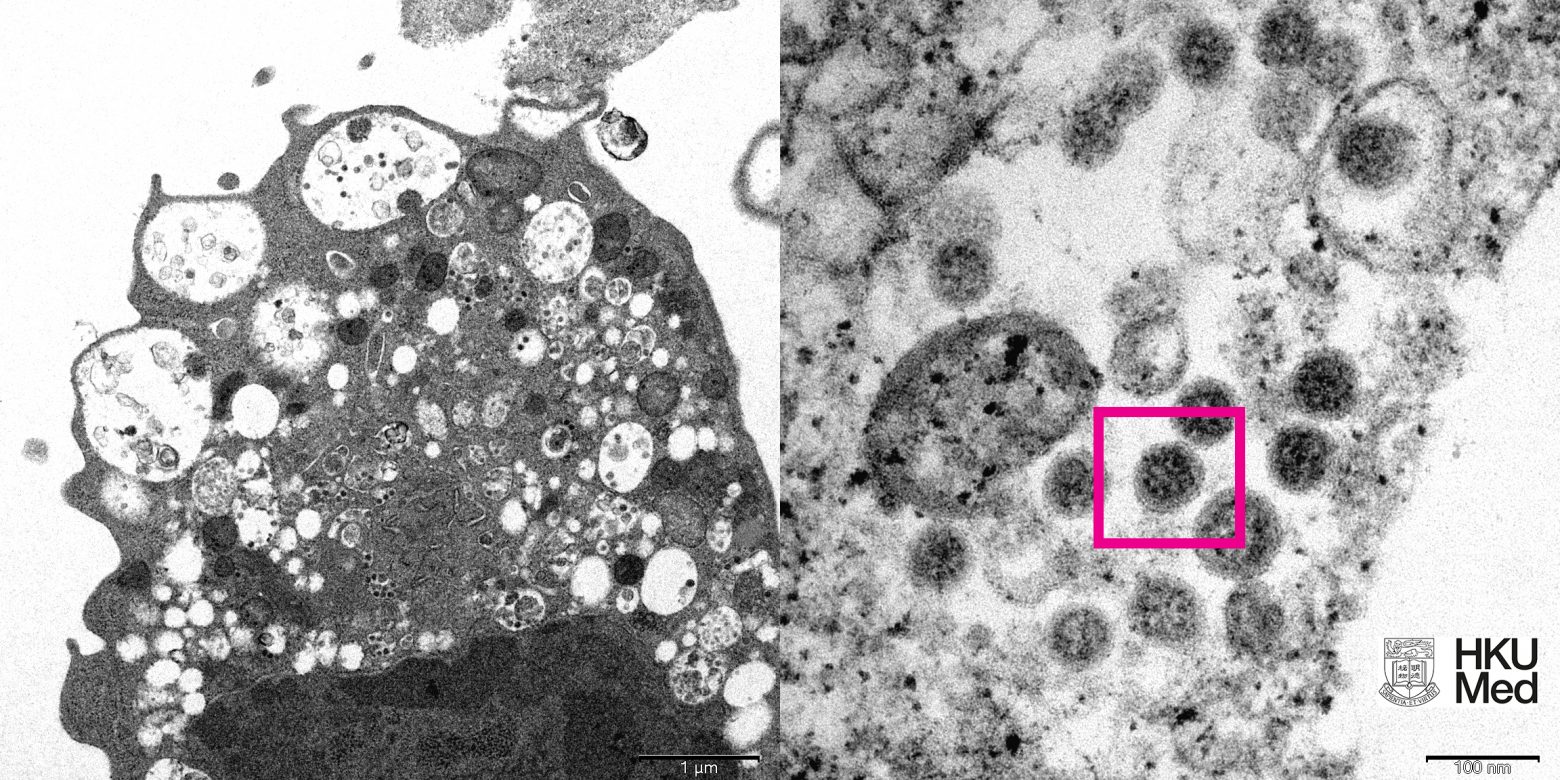

Σύμφωνα με το APA, επιστήμονες στον τομέα της υγείας, συμπεριλαμβανομένων παθολόγων και ιολόγων, κατάφεραν να λάβουν μια ηλεκτρονική μικρογραφία ενός κυττάρου (Vero E6) από το νεφρό ενός πιθήκου που μολύνθηκε με το συγκεκριμένο στέλεχος.

Στη συνέχεια το Πανεπιστήμιο δημοσίευσε τις εικόνες χαμηλής και υψηλής μεγέθυνσης.

Αριστερά, είναι η ηλεκτρονική μικρογραφία χαμηλής μεγέθυνσης κυττάρου νεφρού πιθήκου (Vero E6) μετά από μόλυνση με την παραλλαγή Omicron SARS-CoV-2. Δείχνει κυτταρική βλάβη με διογκωμένα κυστίδια που περιέχουν μικρά μαύρα ιικά σωματίδια.

Δεξιά, είναι η ηλεκτρονική μικρογραφία υψηλής μεγέθυνσης μολυσμένου κυττάρου Vero E6. Δείχνει συγκεντρώσεις ιικών σωματιδίων με αιχμές σχήματος κορώνας στην επιφάνειά τους (κόκκινο πλαίσιο).